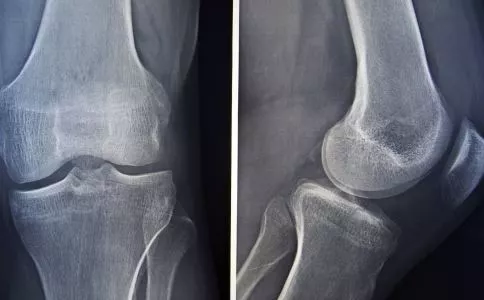

腰背疼痛是腰椎间盘突出吗?

腰背疼痛是人们日常生活中经常遇到的一种病症,这其中很大一部分是由于腰椎间盘突出引起的。这种疾病常见于20-50岁的病人,男女比例约为4:6。

腰椎间盘突出的症状